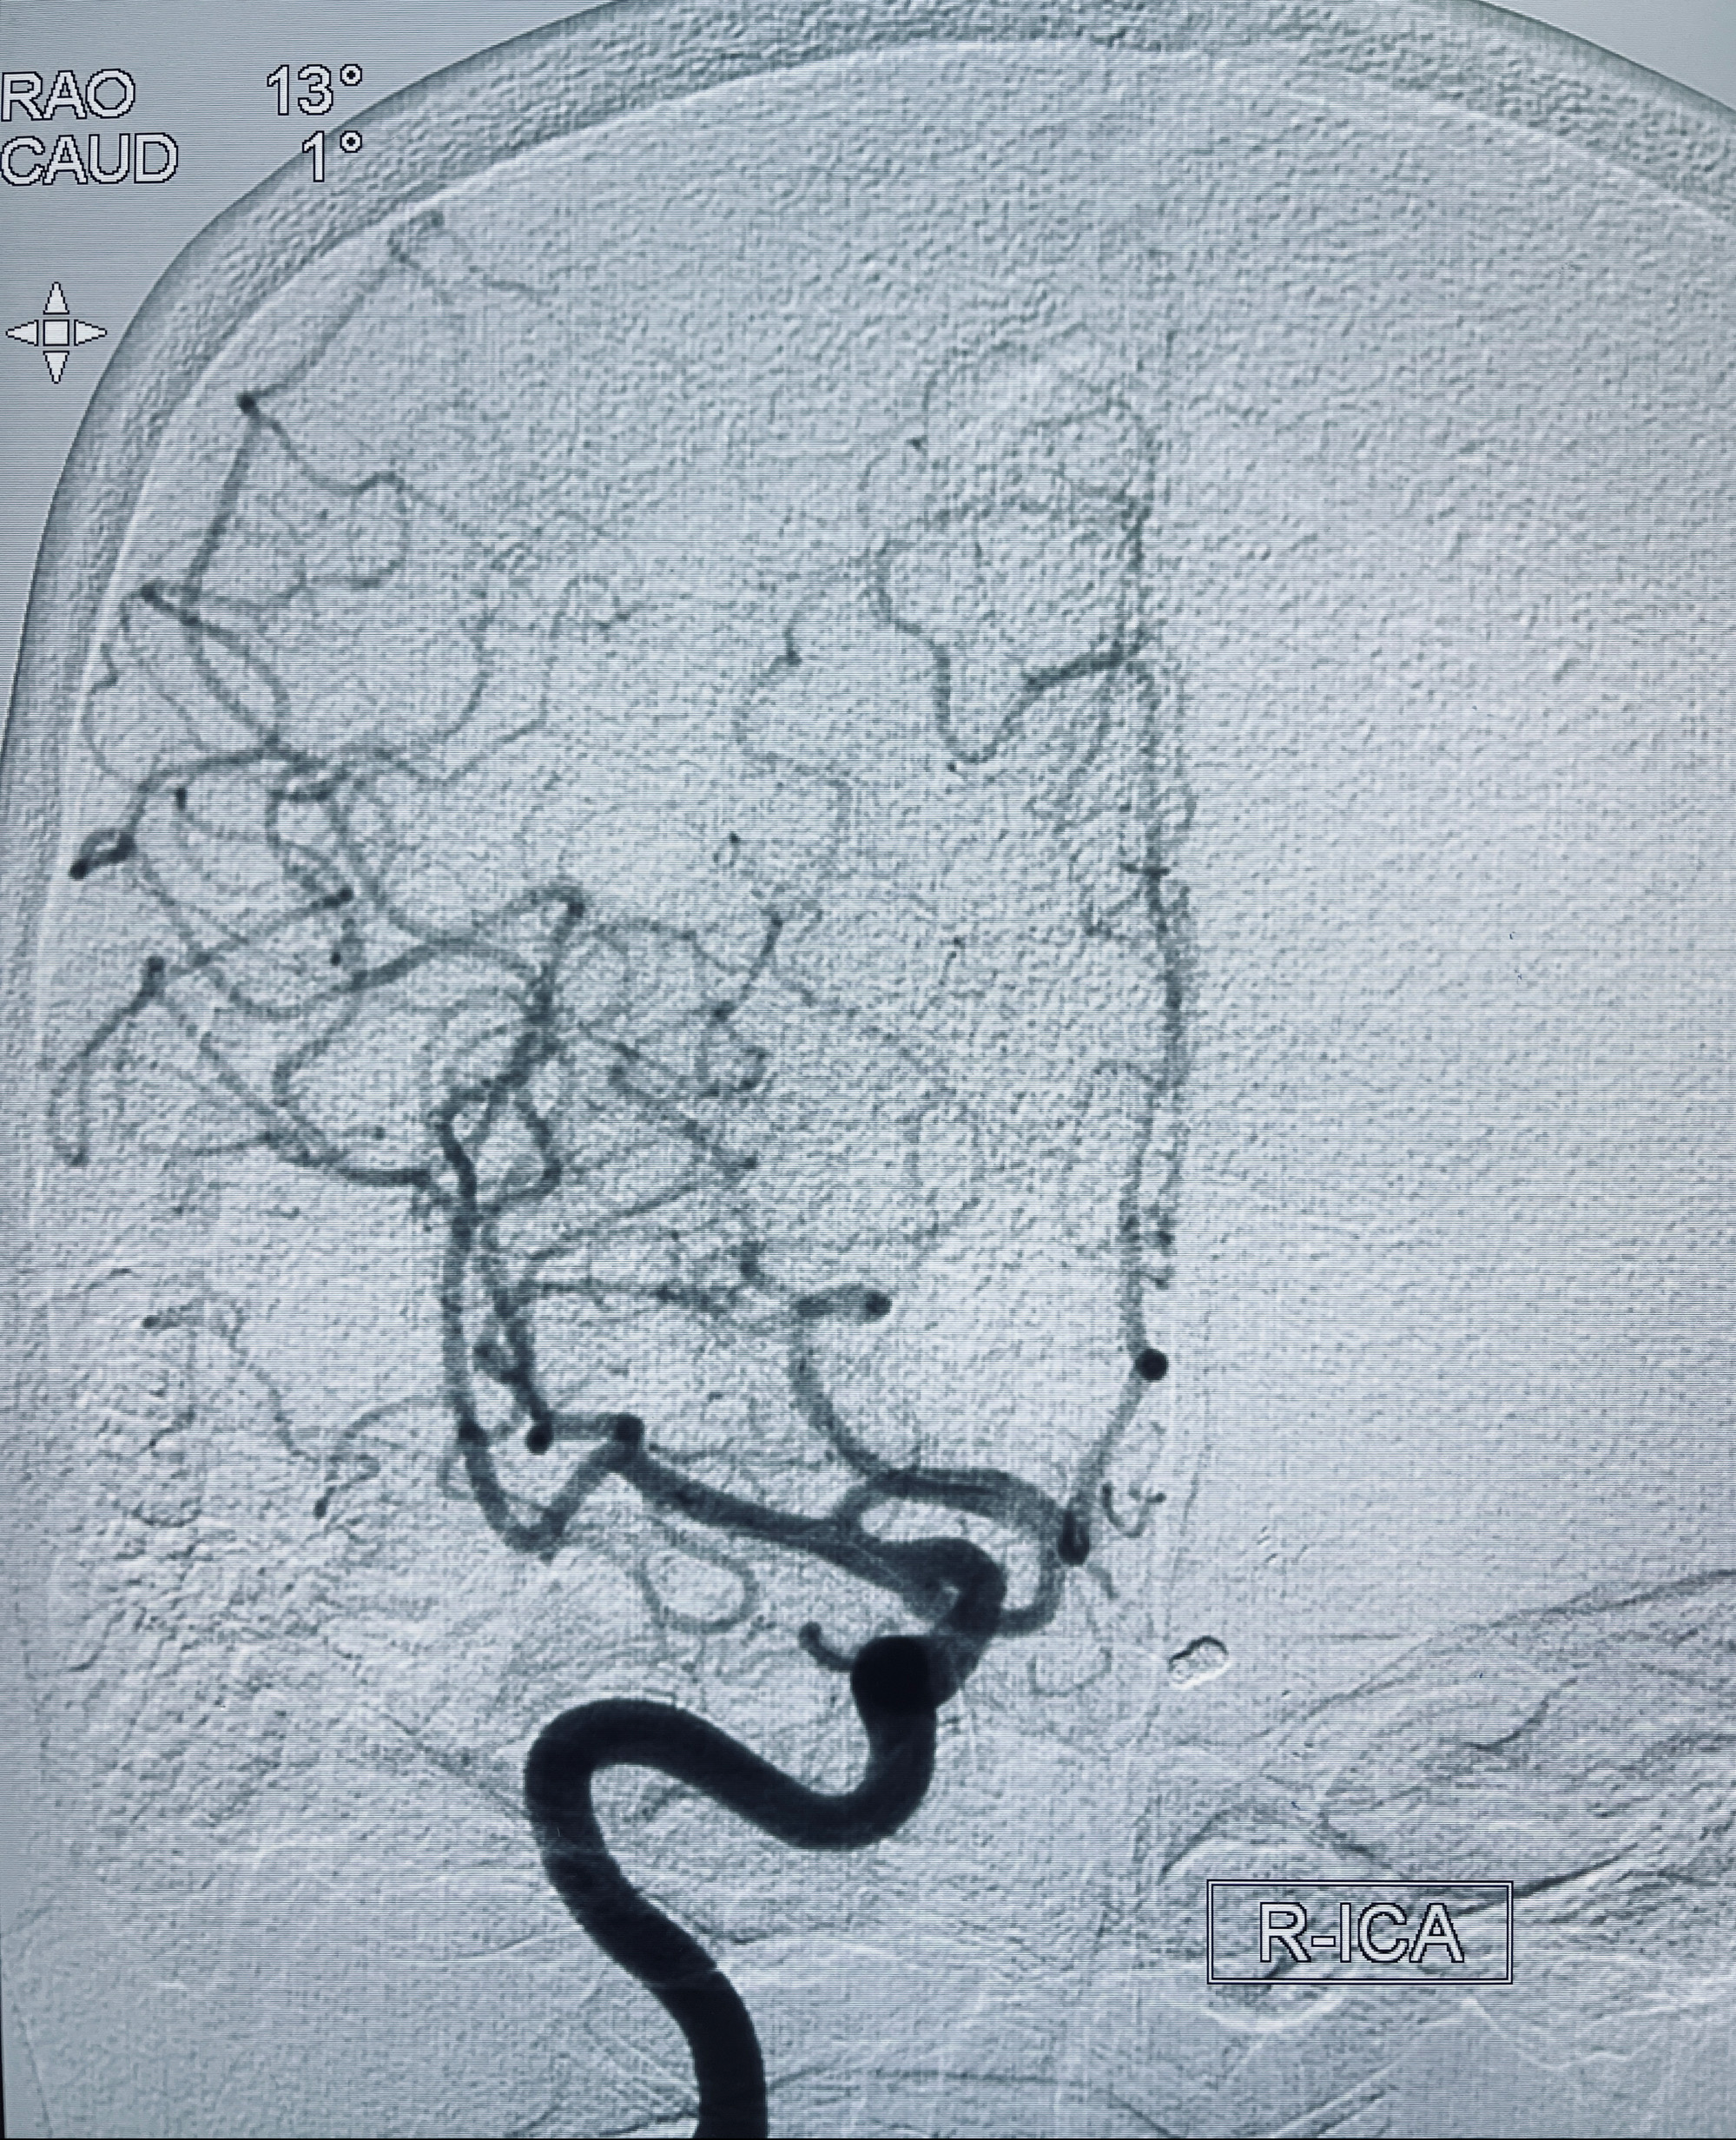

2022-09-29复查DSA